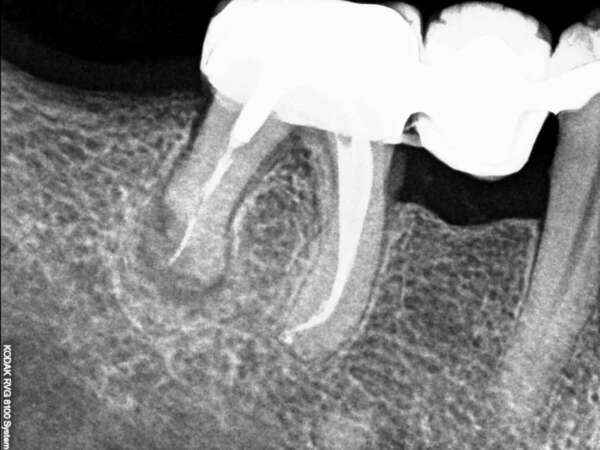

Un kyste sous une couronne, opéré et guérit.

Un kyste condamnant la dent est éliminé par technique laser.